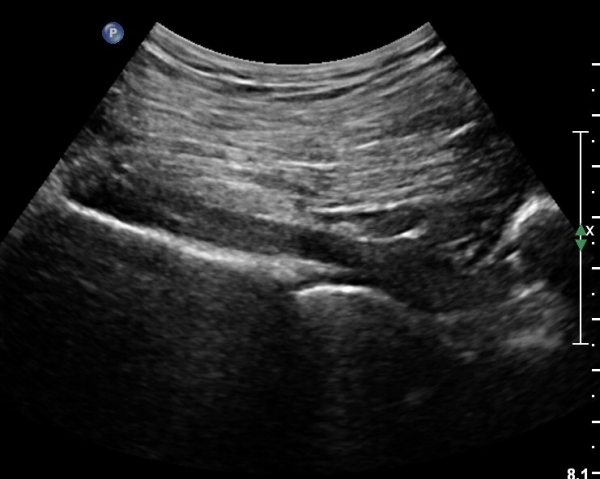

ÈÄ»óÀå°ñ±Ø ¿ÜÃø¿¡ ŽÃÊÀÚ¸¦ ¼öÆòÀ¸·Î ´ë¸é ½ÉÃþÀ¸·Î Àå°ñÀÌ °üÂûµÇ°í Àå°ñ Ç¥Ãþ¿¡ ´ëµÐ±Ù°ú ÁߵбÙÀÌ °üÂûµÈ´Ù(»çÁø 1).